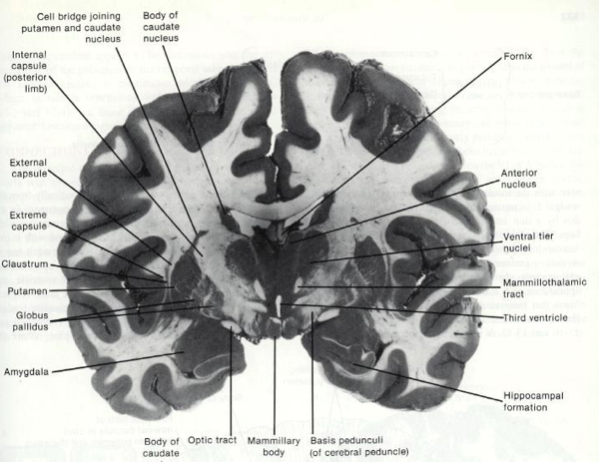

What does the caudate nucleus wrap around?

thalamus

What makes up the lentiform nucleus?

putamen

globus pallidus

What makes up the corpus striatum?

caudate nucelus and lentiform nucleus

What seperates the lentiform nucleus from the caudate nucleus?

internal capsule

Where is the substantia nigra?

in the midbrain

Fill in the blanks